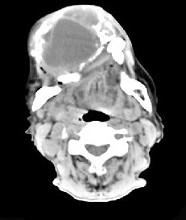

问题 男性,38岁,右侧下颌骨渐进性膨大半年,近来牙齿松动脱落,CT扫描如图所示,请选择最佳答案()

选项 A.动脉瘤样骨囊肿 B.造釉细胞瘤 C.骨软骨瘤 D.牙根囊肿 E.牙龈癌

答案 B